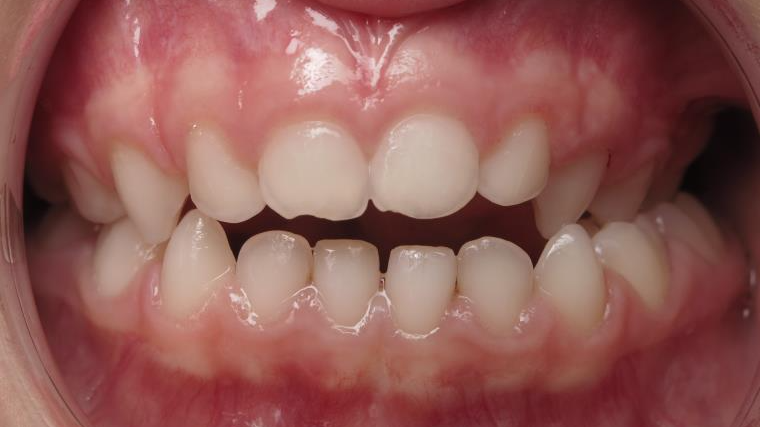

14 béance inversé gauche 5 ans

inversion postérieur coté droit et espace entre l'arcade du haut et du bas (béance)